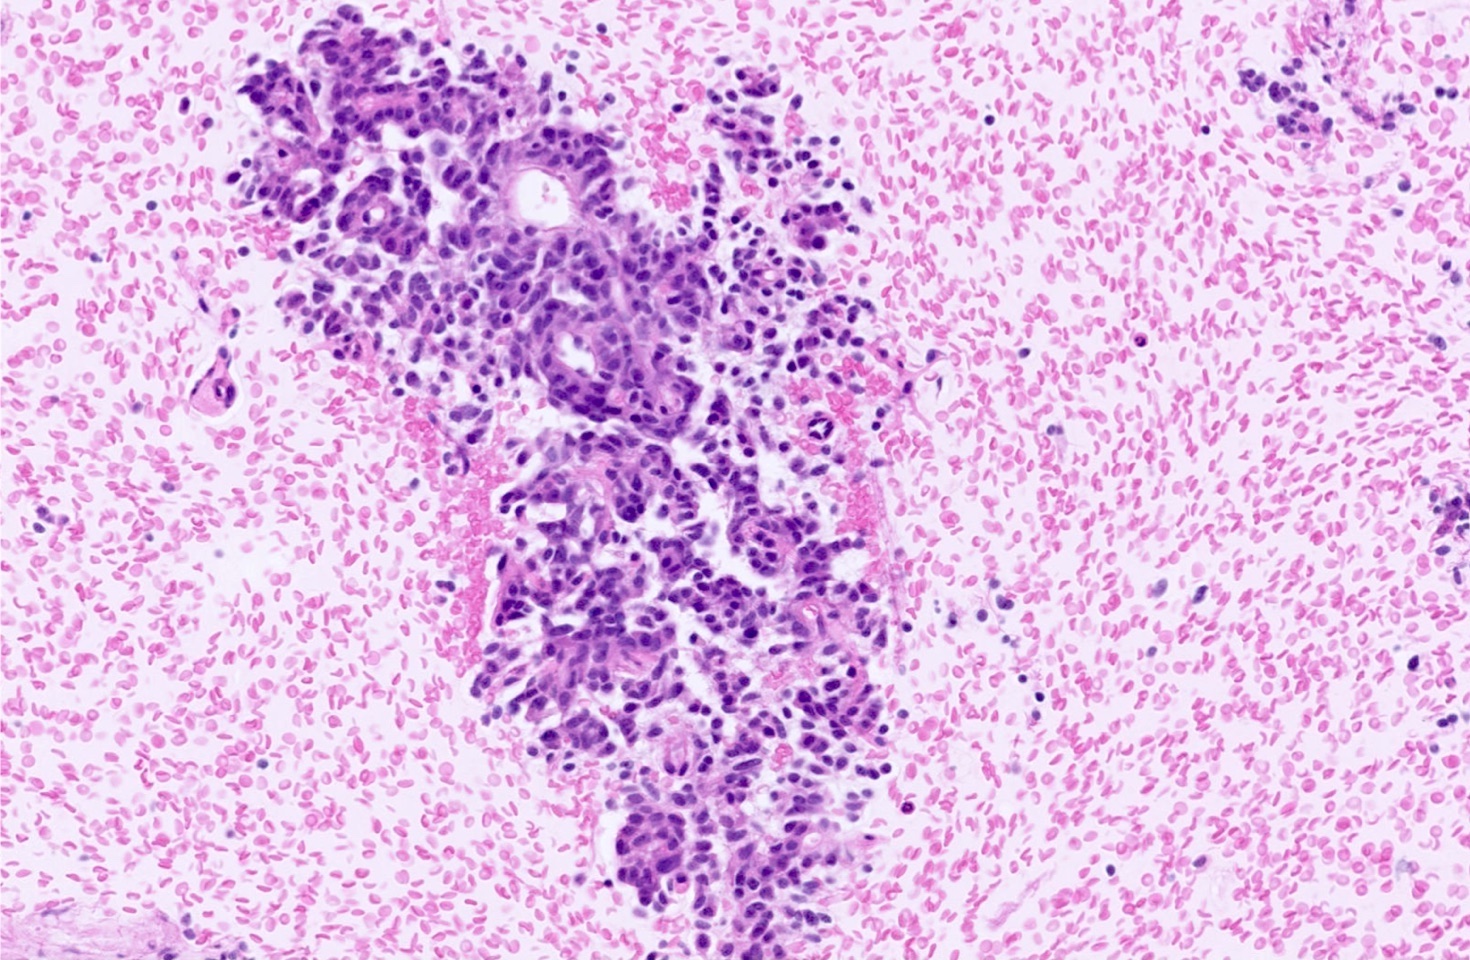

Microscopic (histologic) description

- Diagnostic criteria

- Neuroendocrine tumor with size ≥ 5 mm with < 2 mitoses/2 mm2 and absence of necrosis

- Neuroendocrine growth pattern (organoid, trabecular, rosette formation, nested) or pseudoglandular, follicular and papillary growth

- Tumor cells are uniform with a polygonal shape, round to oval nuclei with salt and pepper chromatin as well as inconspicuous nucleoli and moderate to abundant eosinophilic cytoplasm

- Spindle cells and clear cell features can be seen

- Stroma is fine and highly vascularized; hyalinization, cartilage or bone formation are possible

- Reference: Curr Oncol 2018;25:S86

Microscopic (histologic) images

Contributed by Philippe Joubert, M.D., Ph.D., Jijgee Munkhdelger, M.D., Ph.D. and Andrey Bychkov, M.D., Ph.D.

A 55 year old woman had a lower left lobectomy showing a well circumscribed flesh colored tumor. Histologic details are shown in the image above. Regarding this entity, which of the following statements is true?

A. CDX2 is usually negative in the lung and is useful to differentiate from a metastasis of an intestinal origin. The image shows a tumor with a trabecular pattern and pseudorosettes. The stroma is highly vascularized. Tumor cells are monotonous with scant to moderate eosinophilic cytoplasm. Nuclei are round to oval with salt and pepper chromatin and inconspicuous nucleoli. No mitoses are seen. These features are consistent with a typical carcinoid lung tumor.